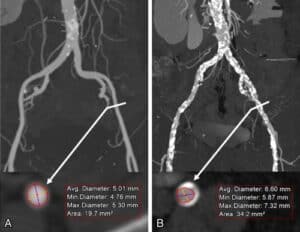

4. Accesos Vasculares:

Así mimo, es posible medir el diámetro y la calcificación de los accesos vasculares para definir la vía idónea para implantar la prótesis. En pacientes con arterias femorales delgadas: no es posible realizar el implante de la TAVI.

tomografía de corazón y medicion de accesos vasculares